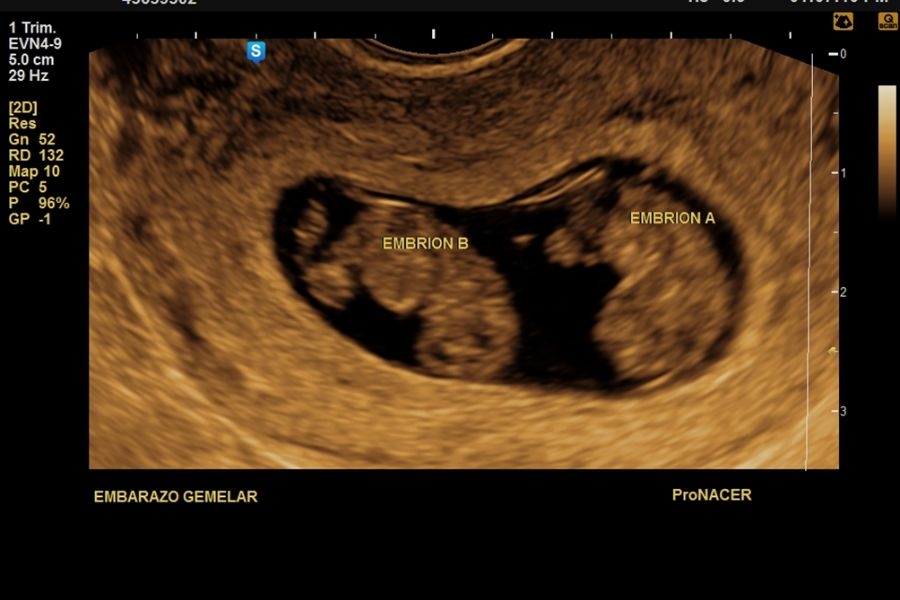

EN EL EMBARAZO MULTIPLE EN GENERAL ES IMPORTANTE QUE SEPAS QUE TIPO ES: MONOCORIAL O BICORIAL

El diagnostico de cigocidad de un embarazo gemelar (si es monocigótico o gemelos idénticos, o bien dicigoto o de mellizos) tiene su importancia, pero no siempre es posible realizarlo.

Lo más importante a la hora de diagnosticar una gestación gemelar es fijarnos en su número de bolsas y en su número de placentas (CORIONICIDAD). Estas características son las que nos van a cambiar el pronóstico de la gestación gemelar y la atención obstétrica durante el embarazo.

Un diagnóstico preciso de la cronicidad (número de placentas) es más importante que su cigocidad (si provienen de la fecundación de 1 o 2 cigotos). Es decir, saber si son gemelos idénticos o mellizos no es tan importante como conocer que elementos comparten (placenta, bolsa) porque es ahí cuando los riesgos cambian.

Se controlan más estrechamente a las gestaciones MONOCORIALES (con una sola placenta). Las gestaciones con gemelos monocoriales son embarazos de mayor riesgo debido al mayor riesgo de complicaciones que pueden tener con respecto a las gestaciones bicoriales (dos placentas).

El momento óptimo para realizar el estudio ecográfico para cronicidad y animosidad es el 1er trimestre a partir de la semana 7, 11 a 14 con una sensibilidad > 98%, con una precisión menor pero aceptable en el segundo trimestre temprano (sensibilidad 90%).